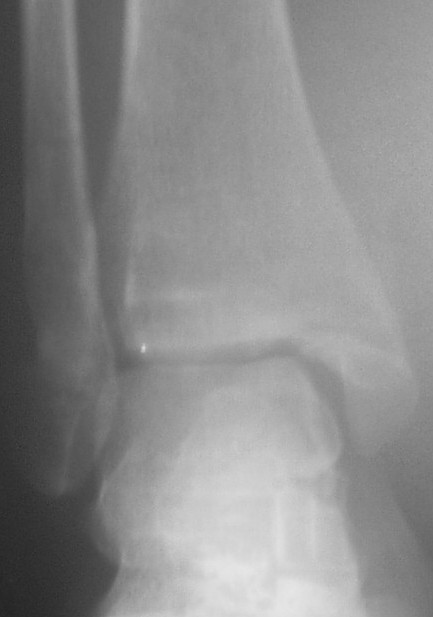

Прямой

На боковом довольно неплохой сустав, скудная информация о положении вилки сустава при косой рентгенограмме (Mortise view) из-за положения стопы во внутренней ротации и эквинуса во время ренгенограммы.

На прямом снимке наружная лодыжка немного укорочена и по описанию на КТ синдесмоз расширен.